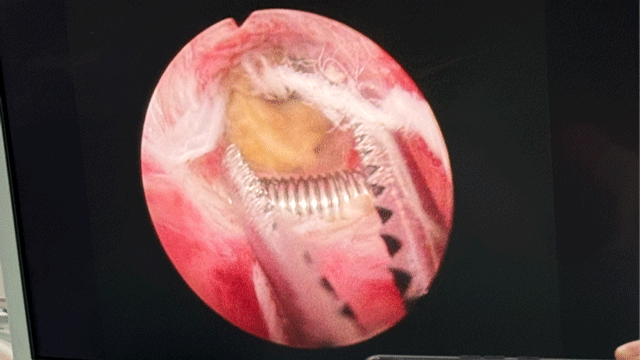

因患者绝经38年,宫颈严重萎缩,住院后予以药物软化宫颈预处理,完善相关辅助检查,请专科会诊排除手术禁忌后,在静脉麻醉下行宫腔镜手术,术中见圆形环大部分嵌顿于肉中,宫内可见残留的似骨性组织,约2*1厘米,在宫腔镜下剪刀分离粘连,将环游离,因嵌顿严重,取出过程中环变形,但环完整取出,用异物钳夹出异物,手术过程顺利,患者全程无痛感。

术中可见宫内环大部分嵌顿

环虽然变形,但完整取出